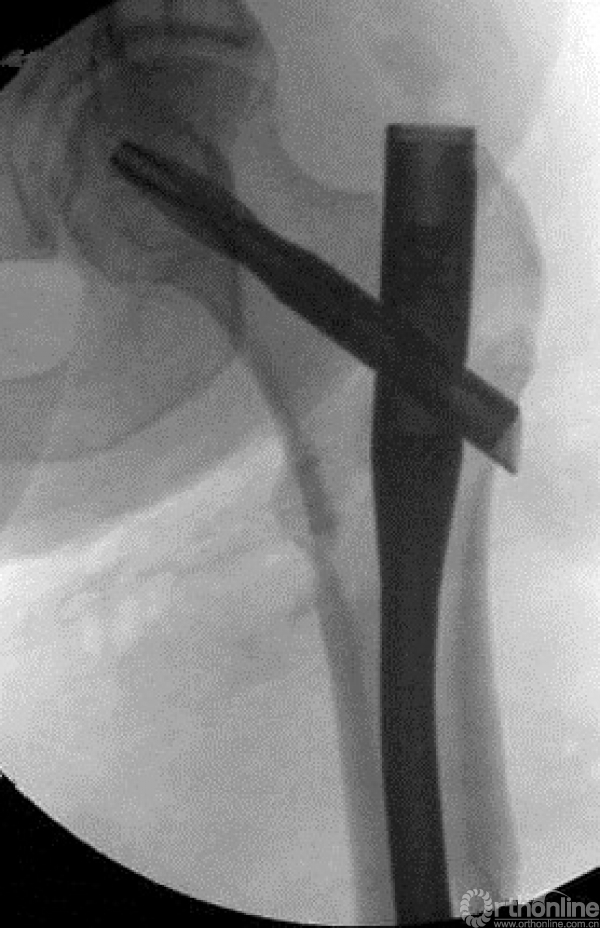

牵引钳加复位后。

微创钳加复位。